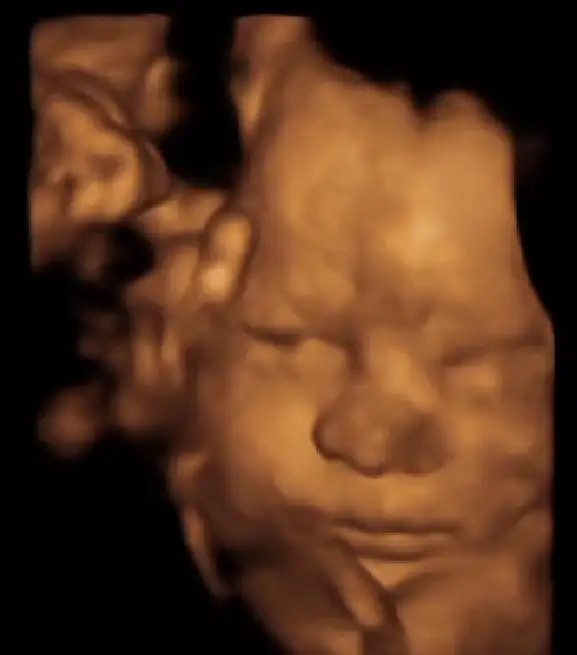

Kızlaarr dün kontrolüm vardı allaha şükür herşey yolunda dün SAT'a göre tam 32+0'dım ama bebek ileride 34+2 ile uyumlu çıkıyor. 2308 kg olmuşuz suyumuz da oldukça iyiymiş :) Doktor 19 Ocaktan sonrasını öngördü :)

Yaa masallah ne guzel pozlar vermis annesii bizimki yuzunu hep plesentaya yasliyor bi eliyle de kalan tarafi kapatiyor 2 aydir sadece yan profilden ayni 1-2 pozu var o kadar bebemin neye benzedigini tam bilmiyorum 🤣🤣 doktor da ugrasiyor baya aman saglikli olsun siz gormeniz gerekeni gorun de biz dogunca goruruz diyorum artik